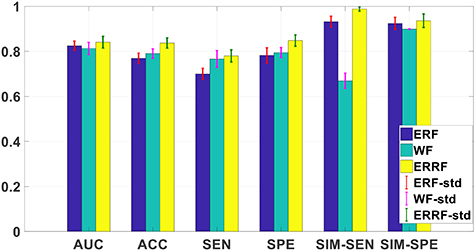

Standard image High-resolution image3.6. Comparative study among three fusion strategies

We compare the model reliability when using different fusion strategies and the results are shown in figure 9. ERRF can obtain best results in six evaluation criteria among three strategies. Compared with another two strategies, the main difference of ERRF is it introduces the model reliability during the fusion process, which makes the model more reliable. Meanwhile, both ERF and ERRF outperform WF. ER is a special case of ER rule (Yang and Xu 2013), which demonstrates that ER rule is an outstanding probabilistic inference tool for information fusion.

Figure 9. The reliability evaluation results for three fusion strategies.

Download figure: